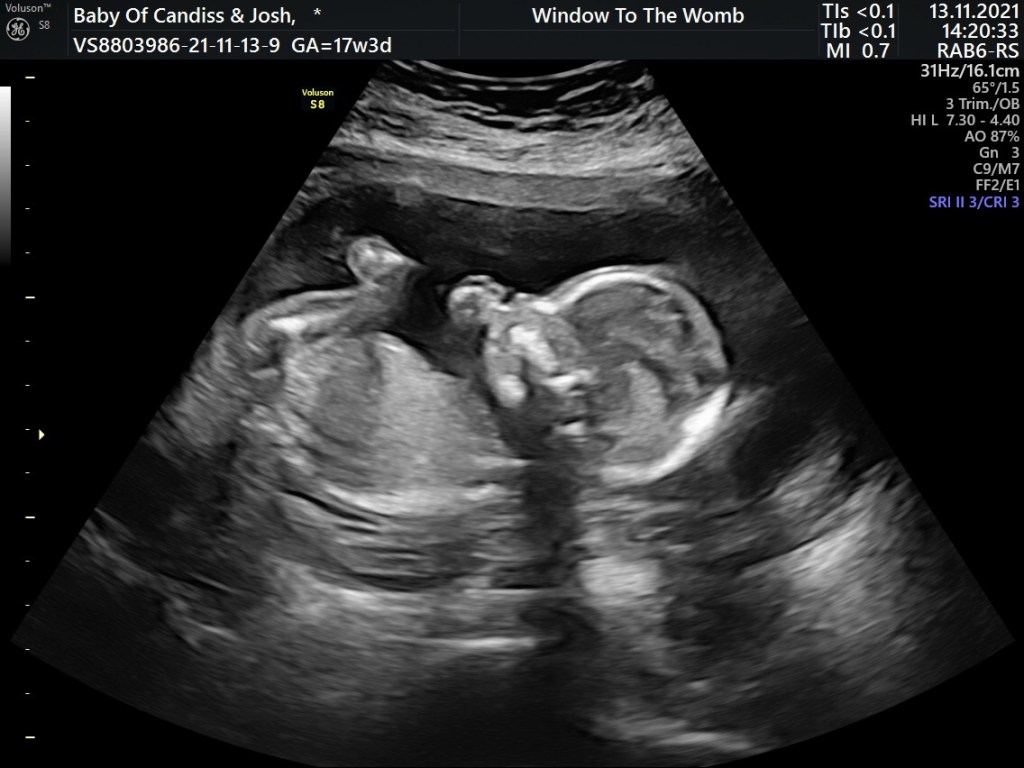

We found out I was pregnant at 17 weeks, long story short was I was on the pill and didn’t know but the dates line up that I got pregnant just after having my first COVID-19 vaccine. Who would have thought it. But we decided it’s never the right time just the right baby and this little girl wanted to be here and we couldn’t be happier.